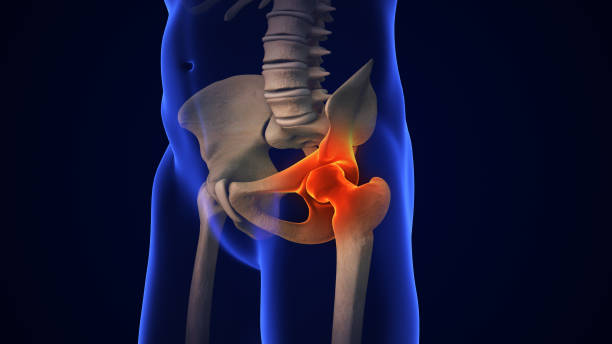

Kyčelní kloub je kulovitý kloub, který je místem kloubu mezi hlavičkou stehenní kosti a pánví. Jedná se o diartrodiální kloub, jehož vnitřní stabilita je dána především jeho kostěnými součástmi/členěními. Primární funkcí kyčelního kloubu je poskytovat dynamickou oporu hmotnosti těla/třídy a zároveň usnadňovat přenos síly a zatížení z osového skeletu na dolní končetiny, což umožňuje pohyblivost.

Kyčelní kloub spojuje dolní končetiny s osovým skeletem. Kyčelní kloub umožňuje pohyb ve třech hlavních osách, které jsou na sebe kolmé. Střed celé osy se nachází v hlavici stehenní kosti. Příčná osa umožňuje pohyb v ohybu a natažení. Podélná osa neboli svislice podél stehna umožňuje vnitřní a vnější rotaci. Sagitální osa neboli osa směřující dopředu dozadu umožňuje abdukci a addukci.

Kromě pohybu kyčelní kloub také umožňuje nošení váhy. Stabilita kyčelního kloubu vyplývá z několika faktorů. Tvar acetabula. Vzhledem k hloubce acetabula může zahrnovat téměř celou hlavici stehenní kosti. Kolem acetabula je další fibrocharlatinový límec, acetabulární labrum, který tyto funkce zajišťuje: